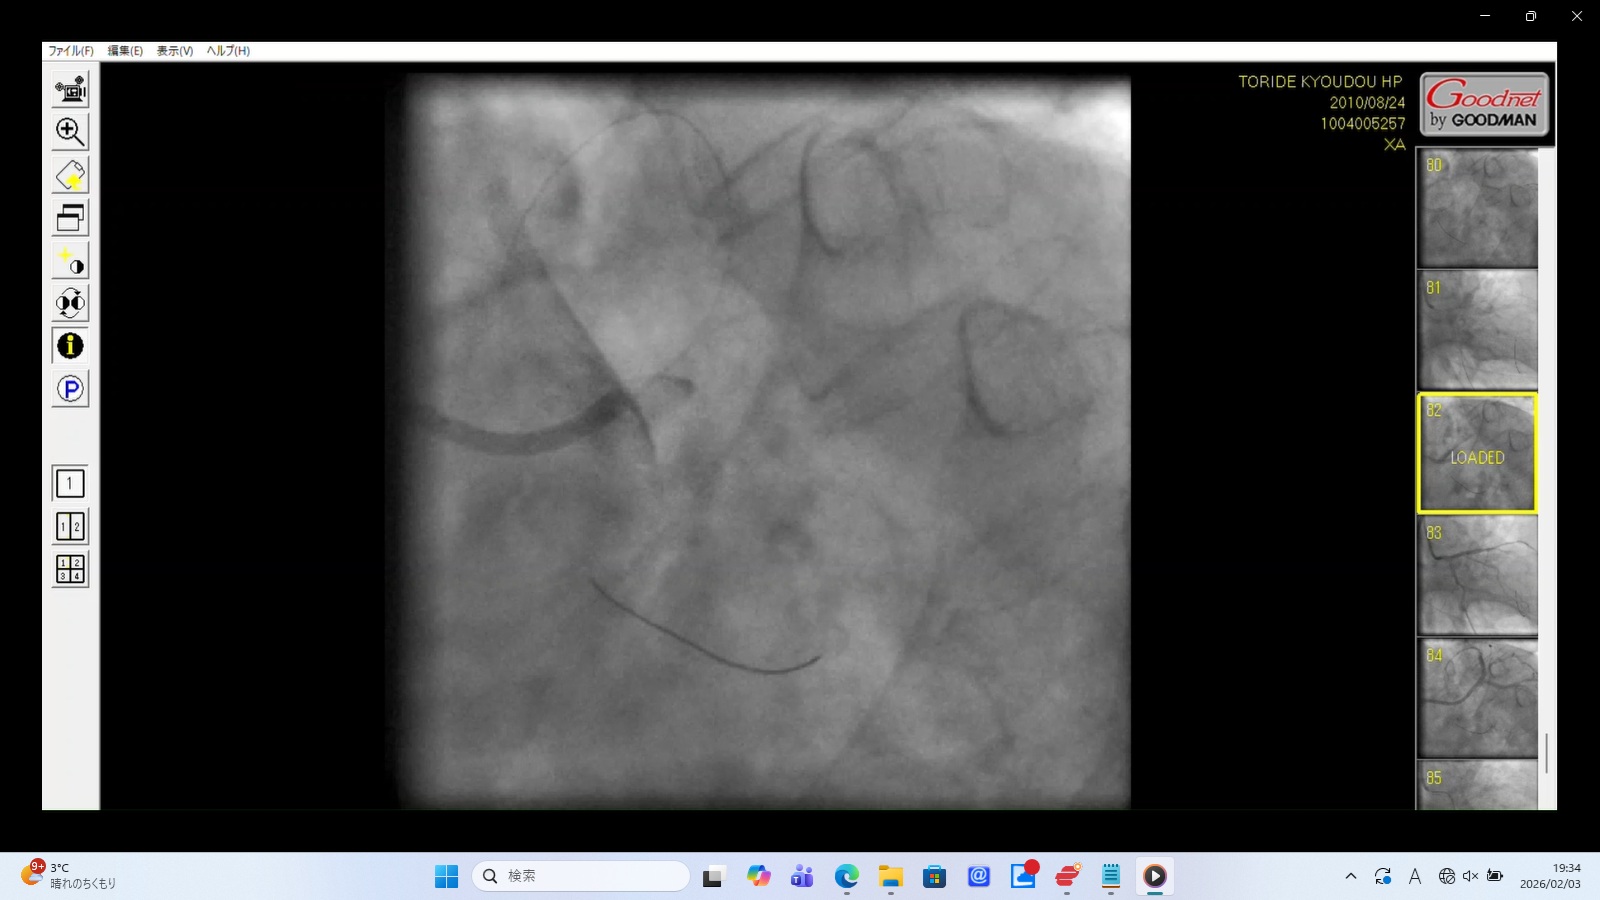

7. XA0082.mp4:左冠動脈主幹部(LMT)の閉塞・損傷(画像をクリックすると動画再生)

画像データ:SHA256:EC60CA2CA6FCDB3C888AC720F35E2D99DD266D604EB03294891DC80173F75491

完全な逆流: 冠動脈入口部(Ostium)に造影剤を注入した瞬間、血管内に入ることなくすべて大動脈へ逆流している。

LMT損傷の疑い: 主幹部での解離(Dissection)やカテーテル先端による機械的損傷によって、入口部が完全に「蓋」をされたような状態を示す。医原性の重度の心筋梗塞であることを示す。